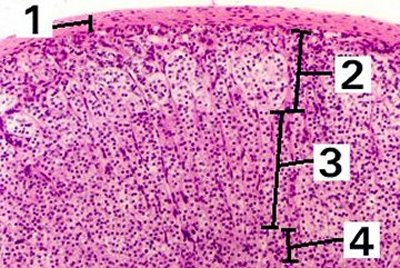

This is an enlargement of the whole cortex of the adrenal gland.

Fig 56-002 1. Capsule

2. Zona glomerulosa

3. Zona fasciculata

4. Zona reticularis